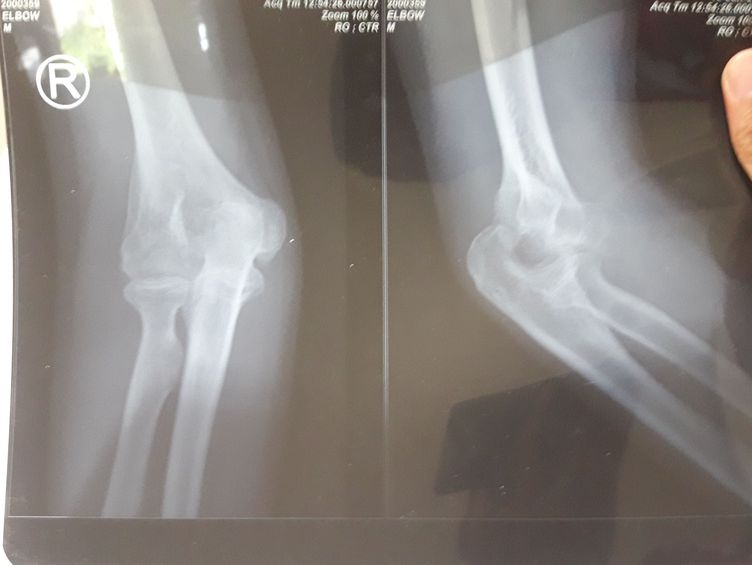

Dis elbow

What actions should be taken for the second operation